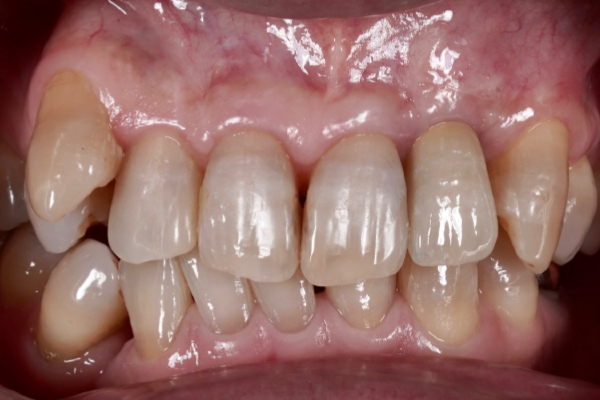

当院では、インプラント治療を行うにあたり歯を失ったところだけではなくお口の中を全体的に検査をします。

その後、コンピューターでシュミレーションを行い、安全でより精度の高いインプラント治療を行っていきます。

インプラントは天然歯よりも感染に弱いため、長く持たせるためにはインプラント周囲の環境を整えることが大変重要になってきます。当院では必要に応じて失われた顎骨・歯肉の再建を行い、予知性の高いインプラント治療を行っていきます。

インプラント治療において私達が大切にしていることは、なぜ歯を失ってしまったかを徹底的に診断することです。

「虫歯で歯を失ってしまったのか?」、「歯周病で歯を失ってしまったのか?」、「かみ合わせの問題があるのかどうか?」等を診断することは非常に大事なことなのです。これらの事は、歯を失ったことは同じですが状況は全く異なるのです。

私達は歯を失ってしまった原因を追求し、インプラント治療、虫歯治療、歯周病治療、矯正治療、根管治療等の治療を組み合わせ総合的に治療計画を立てて治療を行っていきます。